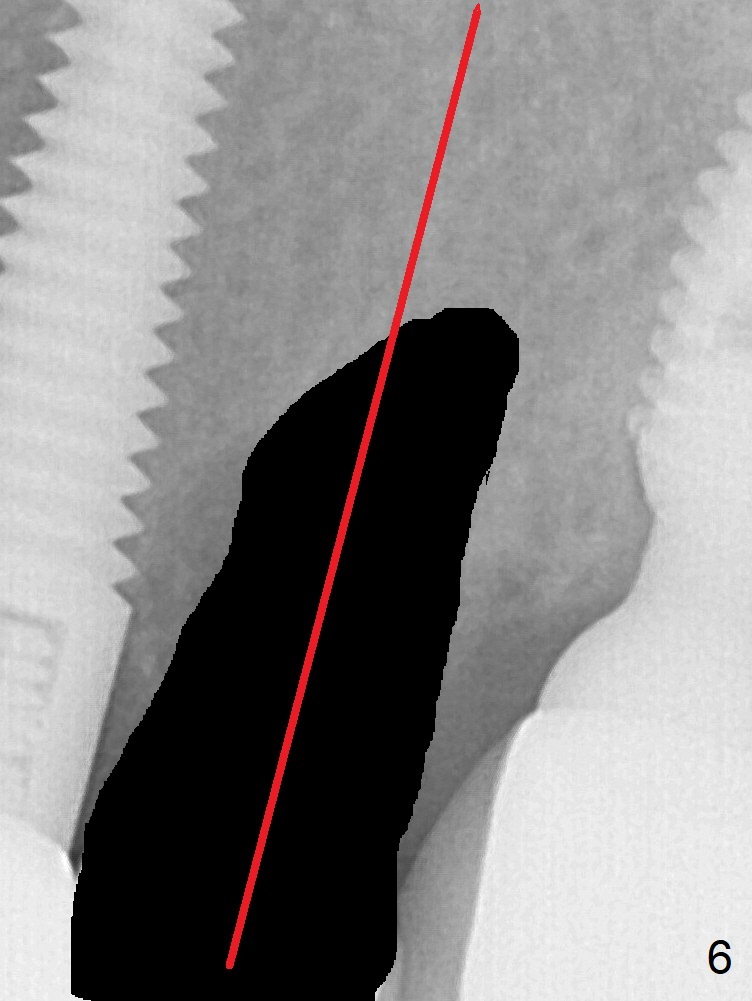

A 59-year-old woman has mild discomfort in the upper left quadrant, which is alleviated by salt water rinse. The buccal gingiva recedes at #13 with mesiobuccal swelling and deep pocket (Fig.1,3), corresponding to the mesial radiolucency (Fig.2 *). The tooth appears to have vertical fractured root, as related to the retention post. Since the root tip curves distal, the initial osteotomy (Fig.5 red) should be established in the mesioapical slope after extraction (black). Following initial entrance, the trajectory will be changed to the long axis of the space (Fig.6) with PA to be taken. Measure the depth of the buccal crest against the buccal, proximal and palatal gingival margins. Place an implant, the same as #12 (4.5x20 mm) unless the mesiobuccal defect is extremely large (UF).